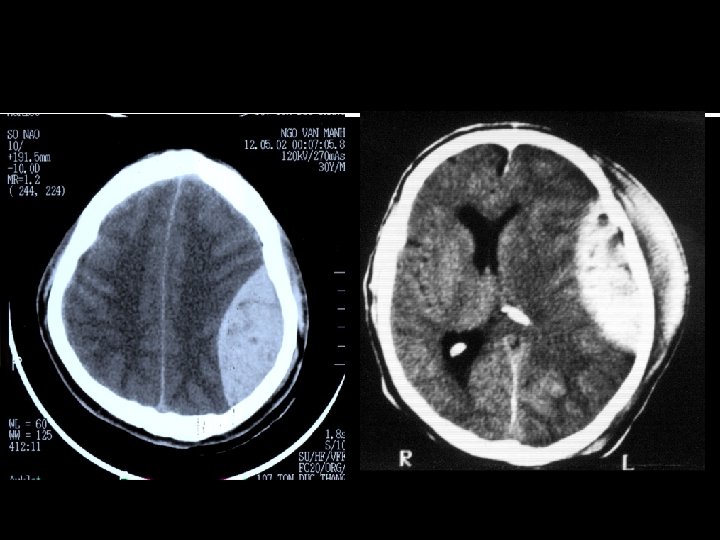

BỆNH ÁN MINH HỌA: -Bệnh nhân NGUYỄN VĂN D. -NAM, 20 TUỔI -ĐC: LƯƠNG TÀI -TAI NẠN GIAO THÔNG DO RƯỢU -VV: 13/7 Tỉnh táo hoàn toàn, GCS 15 điểm - Chup CLVT: KHÔNG CÓ MÁU TỤ

BN NGYỄN VĂN D -NGÀY 20/7( sau 5 ngày): XUẤT HIỆN ĐAU ĐẦU, HÔN MÊ -TỬ VONG (KHÔNG KỊP CHỤP CẮT LỚP VI TÍNH) -MỔ XÁC: MÁU TỤ TRONG NÃO -GIA ĐÌNH BỆNH NH N KHIẾU KIỆN TẠI SAO BỆNH NH N TỬ VONG ? ? ?

CTSN NGUY CƠ THẤP CHỤP CẮT LỚP VI TÍNH: -XÁC ĐỊNH CHÍNH XÁC TỔN THƯƠNG -ĐƯA RA QUYẾT ĐỊNH HỢP LÝ -TIÊN LƯỢNG ĐÚNG -BẰNG CHỨNG KHOA HỌC -GIẢI THÍCH MỌI DIỄN BIẾN -GIẢI THÍCH CHO GIA ĐÌNH BỆNH NH N

CTSN NGUY CƠ THẤP MỔ: NẾU L M SÀNG NẶNG HƠN VÀ CÓ DẤU HIỆU CHÈN ÉP TRÊN CLVT L M SÀNG NẶNG HƠN: -TRI GIÁC XẤU ĐI -LIỆT TĂNG DẦN -ĐAU ĐẦU -NÔN, BUỒN NÔN -CHÓNG MẶT -NHÌN ĐÔI, LÁC… CẮT LỚP VI TÍNH MÁU TỤ, DẬP NÃO…